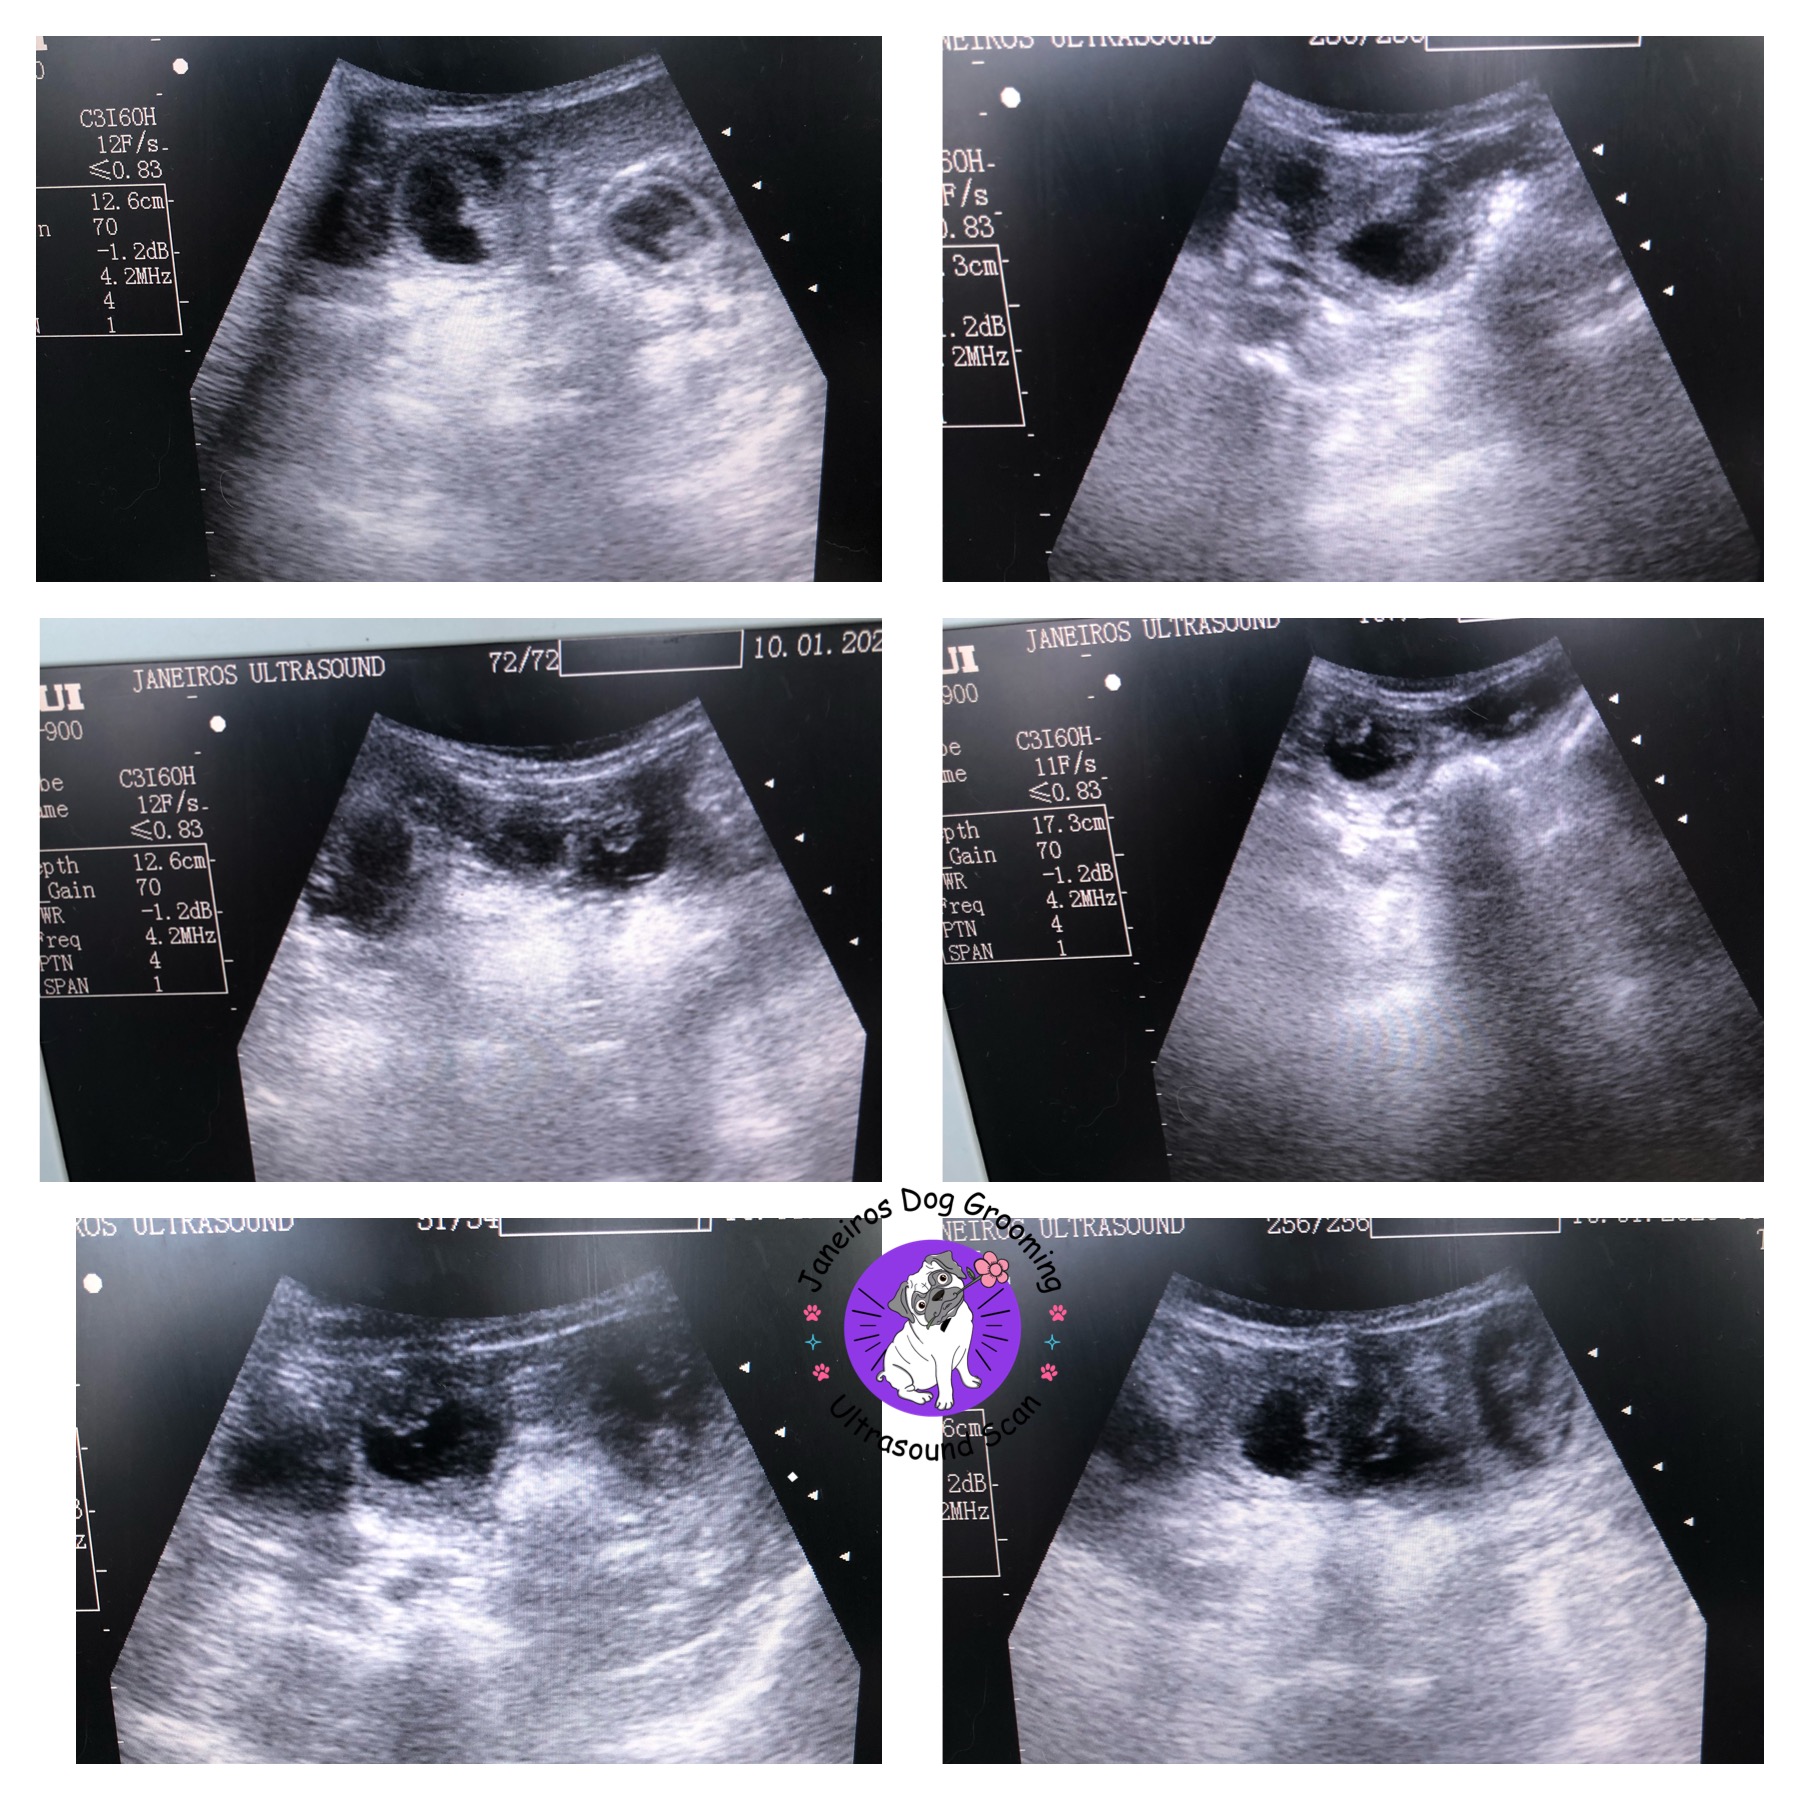

Scan on 7 week dachshund Animal Ultrasound Association

Scan on 7 week dachshund Animal Ultrasound Association Dachshund Ultrasound Ultrasound of a dachshund at approximately 33 days gestation. They are visible on an ultrasound, particularly their little spines. The vet should be able to determine the number of puppies your dachshund will have, as well as any potential abnormalities. The pups continue to grow during this stage. Your vet can perform an ultrasound to confirm the pregnancy and check. Dachshund Ultrasound.